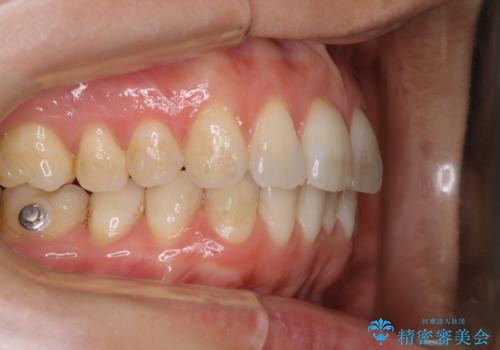

- インビザライン矯正治療中にステインが気になるとのことで来院されました。全体的にステインが付着していたため自費クリーニングPMTC(60分コース)を行いました。

インビザライン矯正治療中は、ご自身の歯にアタッチメントという突起物(効率的に歯の移動を行うため)をつけます。そのため、通常時よりもステインが付きやすい状態になることがあります。